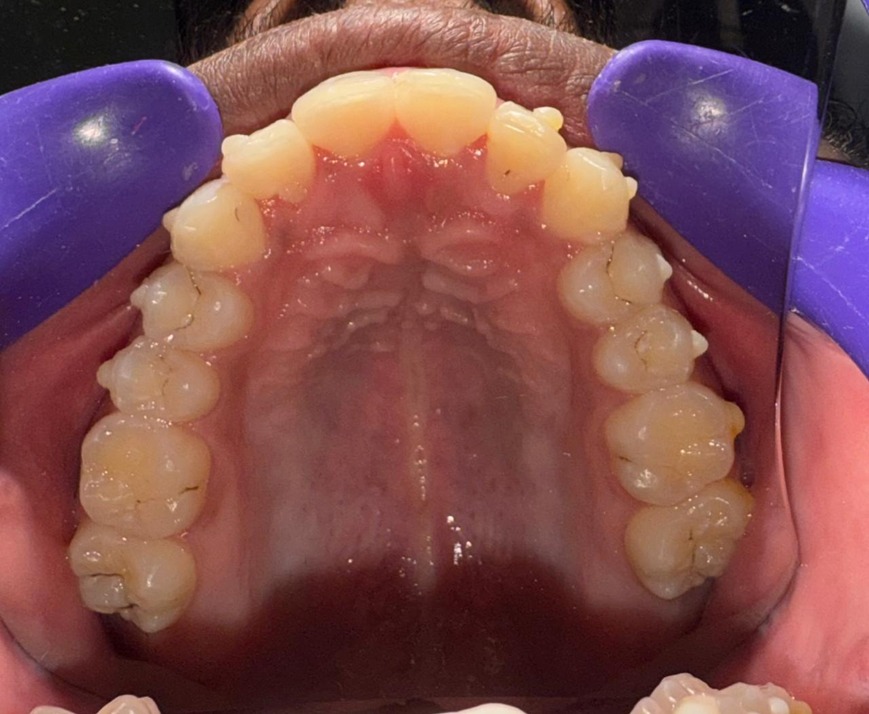

Before & After Results

At Aline Dent, we take pride in delivering visible and lasting improvements in our patients’ smiles. Our before-and-after results highlight the effectiveness of modern dental treatments combined with personalized care. This gallery showcases real dental cases treated at our clinic, giving you a clear idea of how different dental concerns can be corrected with the right treatment approach.

From minor corrections to complete smile enhancements, these teeth transformation results demonstrate how professional dental care can improve both oral health and appearance. Our experienced dental team carefully evaluates each patient’s needs and creates customized treatment plans to achieve natural, healthy, and confident smiles.

In this gallery, you will find a variety of smile makeover cases, including treatments for crooked teeth, gaps, discoloration, damaged teeth, and other common dental concerns.